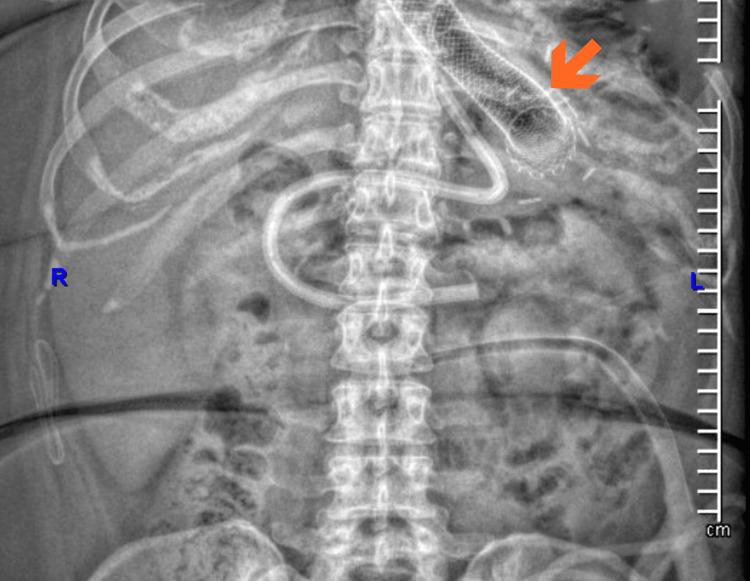

Esophagogastric fistulas are a rare but serious complication after sleeve gastrectomy. Their management remains a clinical challenge, especially when conventional endoscopic approaches, such as stent placement, fail. We report the case of a 49-year-old female with a history of hypothyroidism, major depressive disorder, body mass index greater than 50 kg/m², significant smoking history, and obstructive sleep apnea, who developed acute abdominal pain and bleeding after laparoscopic sleeve gastrectomy. She was referred to our institution in hypovolemic shock and underwent exploratory laparotomy with abdominal packing. An upper endoscopy revealed a 5-10 mm esophagogastric leak initially managed with a covered self-expanding stent, which subsequently migrated. The persistent fistula was confirmed by contrast study, and endoscopic negative pressure therapy (endoscopic vacuum-assisted closure (EndoVAC)) was initiated using a polyurethane sponge with scheduled replacements. After six sessions, complete fistula closure was achieved, confirmed by endoscopic and radiographic evaluation. This case highlights the successful use of EndoVAC therapy as a minimally invasive and effective option for managing refractory post-bariatric esophagogastric fistulas. Early consideration of this technique may improve outcomes in similar scenarios.

食管胃瘘是袖状胃切除术后一种罕见但严重的并发症。其治疗仍然是一项临床挑战,尤其是当传统的内镜治疗方法(如支架置入)失败时。我们报告一例49岁女性病例,该患者有甲状腺功能减退、重度抑郁症病史,体重指数大于50kg/m²,有大量吸烟史及阻塞性睡眠呼吸暂停,在腹腔镜袖状胃切除术后出现急性腹痛和出血。她因低血容量性休克被转诊至我院,接受了剖腹探查并进行腹腔填塞。上消化道内镜检查发现一个5 - 10毫米的食管胃瘘,最初采用覆膜自膨式支架治疗,但支架随后移位。通过造影检查证实存在持续性瘘,遂开始使用聚氨酯海绵进行内镜负压治疗(内镜真空辅助闭合术(EndoVAC))并定期更换。经过六次治疗后,通过内镜和影像学评估证实瘘完全闭合。该病例突出了EndoVAC治疗作为一种微创且有效的方法成功用于处理减重术后难治性食管胃瘘。在类似情况下,早期考虑这种技术可能会改善治疗效果。